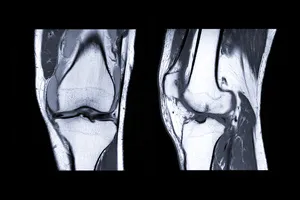

반월상 연골 손상

반월상 연골 손상은 무릎 관절 안쪽에 반달 모양의 연골이 찢어져 발생하는 질환입니다. 손상된 연골 조각이 관절 내에서 끼이거나 마찰되면서 갑작스럽고 날카로운 통증을 유발합니다. 특히 무릎을 구부리거나 회전할 때 통증이 심해집니다.

손상된 연골 조각이 관절 사이에 끼여 무릎이 갑자기 잠기거나 펴지지 않는 현상이 발생할 수 있습니다. 무릎을 반복적으로 사용하는 직업이나 운동을 하는 사람들에게 발생할 수 있습니다.

십자인대 손상

십자인대 손상은 무릎 관절의 안정성을 유지하는 데 중요한 역할을 하는 인대가 끊어지는 것을 말합니다. 이러한 손상은 갑작스러운 외력이나 반복적인 스트레스에 의해 발생합니다.